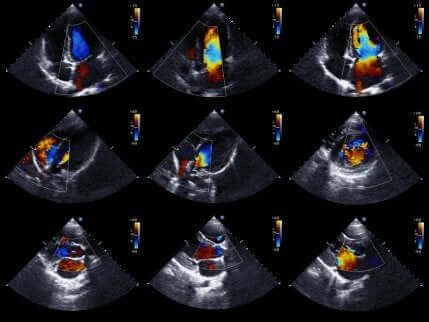

Echocardiogram

Ten slotte stelt een echocardiogram artsen in staat om de werking van het hart gedetailleerder te bestuderen. Het is dezelfde techniek die men gebruikt voor het maken van een echo bij zwangere vrouwen.

Het is dan ook een zeer populaire medische test. Over het algemeen is het een niet-invasieve test die geen risico voor de patiënt met zich meebrengt. Dit komt omdat het echografie gebruikt om de afbeeldingen van het hart te maken.

Zo kan de arts zowel de status van de hartkamers als de bewegingen van het hart evalueren om ischemie te bevestigen of uit te sluiten. Bovendien kan men aan de hand van deze beelden ook de hartgrootte en sterkte en de toestand van de wanden van de hartkamers beoordelen.

Als de arts deze test gebruikt, sluit de afwezigheid van bewegingsstoornissen in de hartwand de aanwezigheid van ischemie uit. Het bestaan van bewegingsstoornissen is immers niet uniek voor acuut coronair syndroom. Om die reden moeten de testresultaten en symptomen gezamenlijk worden beoordeeld.